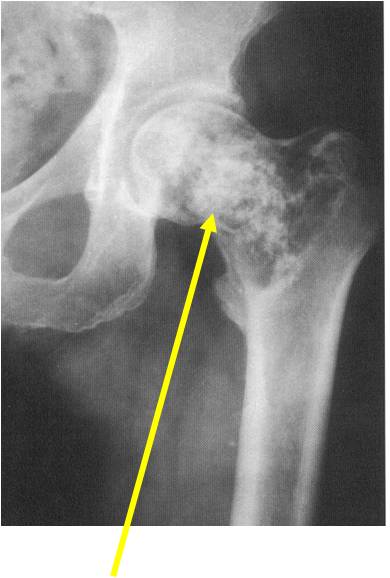

Radiographic Presentation

- Usually osteolytic, expansile lesion

- May be focally calcified

- Often a sharp interface between tumor and surrounding bone

- Sclerotic rim is uncommon

- Overlying cortex is usually thin, but intact